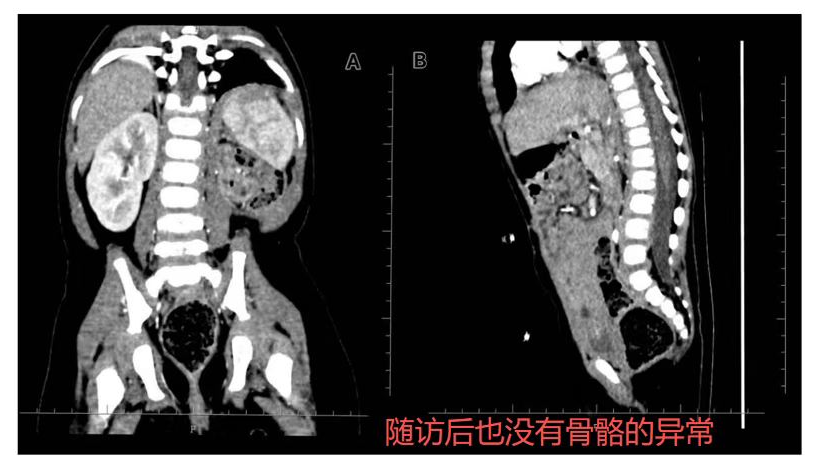

“团队特别注重精准剂量控制。采用IMPT(Intensity Modulated Proton Therapy)技术,严格控制重要脏器的辐射剂量,尤其是对患儿唯一功能肾的辐射剂量,确保其平均剂量控制在<1.5 Gy,从而最大限度地保护了肾脏的功能。”

“此外,团队在治疗过程中针对脊柱及生长板的精准照射做了充分优化。通过剂量学优化设计,显著降低了脊柱和生长板的辐射剂量,确保了在治疗后1年的随访中,患儿未见明显的脊柱侧弯或生长抑制。”

值得高兴的是,经过1年的随访,患儿无肿瘤复发,肾功能和肝功能持续保持在正常范围,进一步验证了质子治疗的长期安全性与疗效。这一结果不仅证明了治疗的有效性,也为质子治疗在高风险婴幼儿群体中的应用提供了更强的支持。